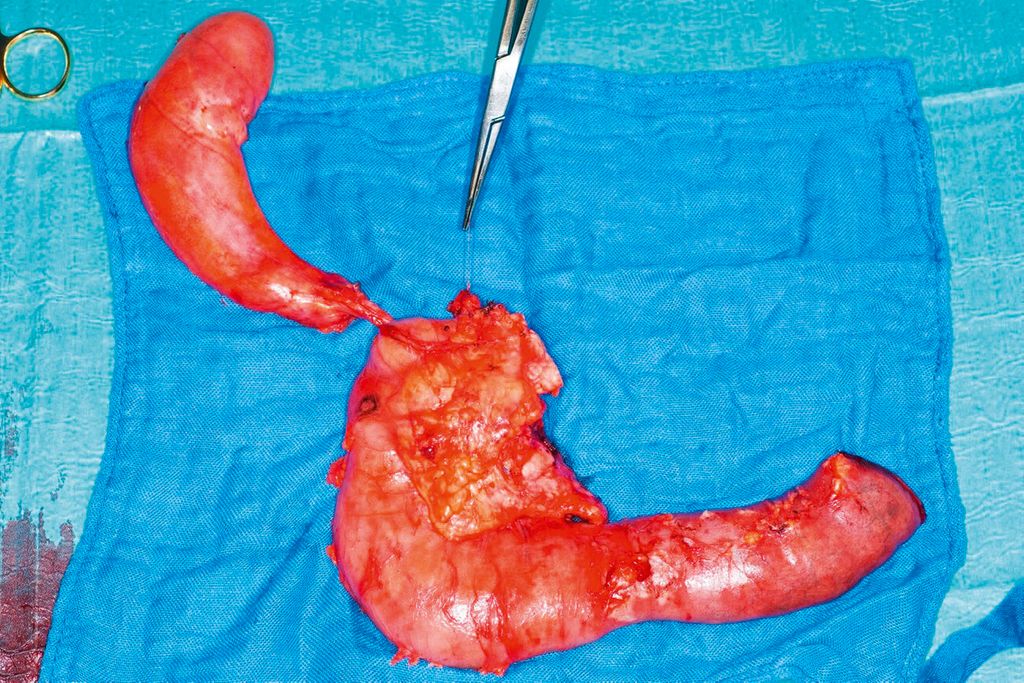

Pankreaslinksresektion

Pankreaskarzinome, die im Bereich des Pankreaskorpus oder der Cauda lokalisiert sind, werden mittels Pankreaslinksresektion und Splenektomie reseziert. Dabei kann je nach Lokalisation des Tumors auch eine subtotale Pankreatektomie notwendig sein. Auch bei der Pankreaslinksresektion wird eine standardisierte Lymphadenektomie durchgeführt (Abb. 2).

Abb. 2: Auch bei der Pankreaslinksresektion wird eine standardisierte Lymphadenektomie durchgeführt